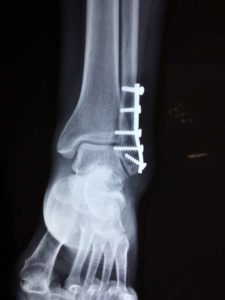

Pokud jste tedy utrpěli v letošním roce dopravní nehodu, pak hodnota jednoho bodu odškodnění bolesti bude činit částku ve výši 356,11 Kč. Například při zlomenině kyčelní kosti bude základní odškodnění bolesti ve výši 53.417,- Kč.